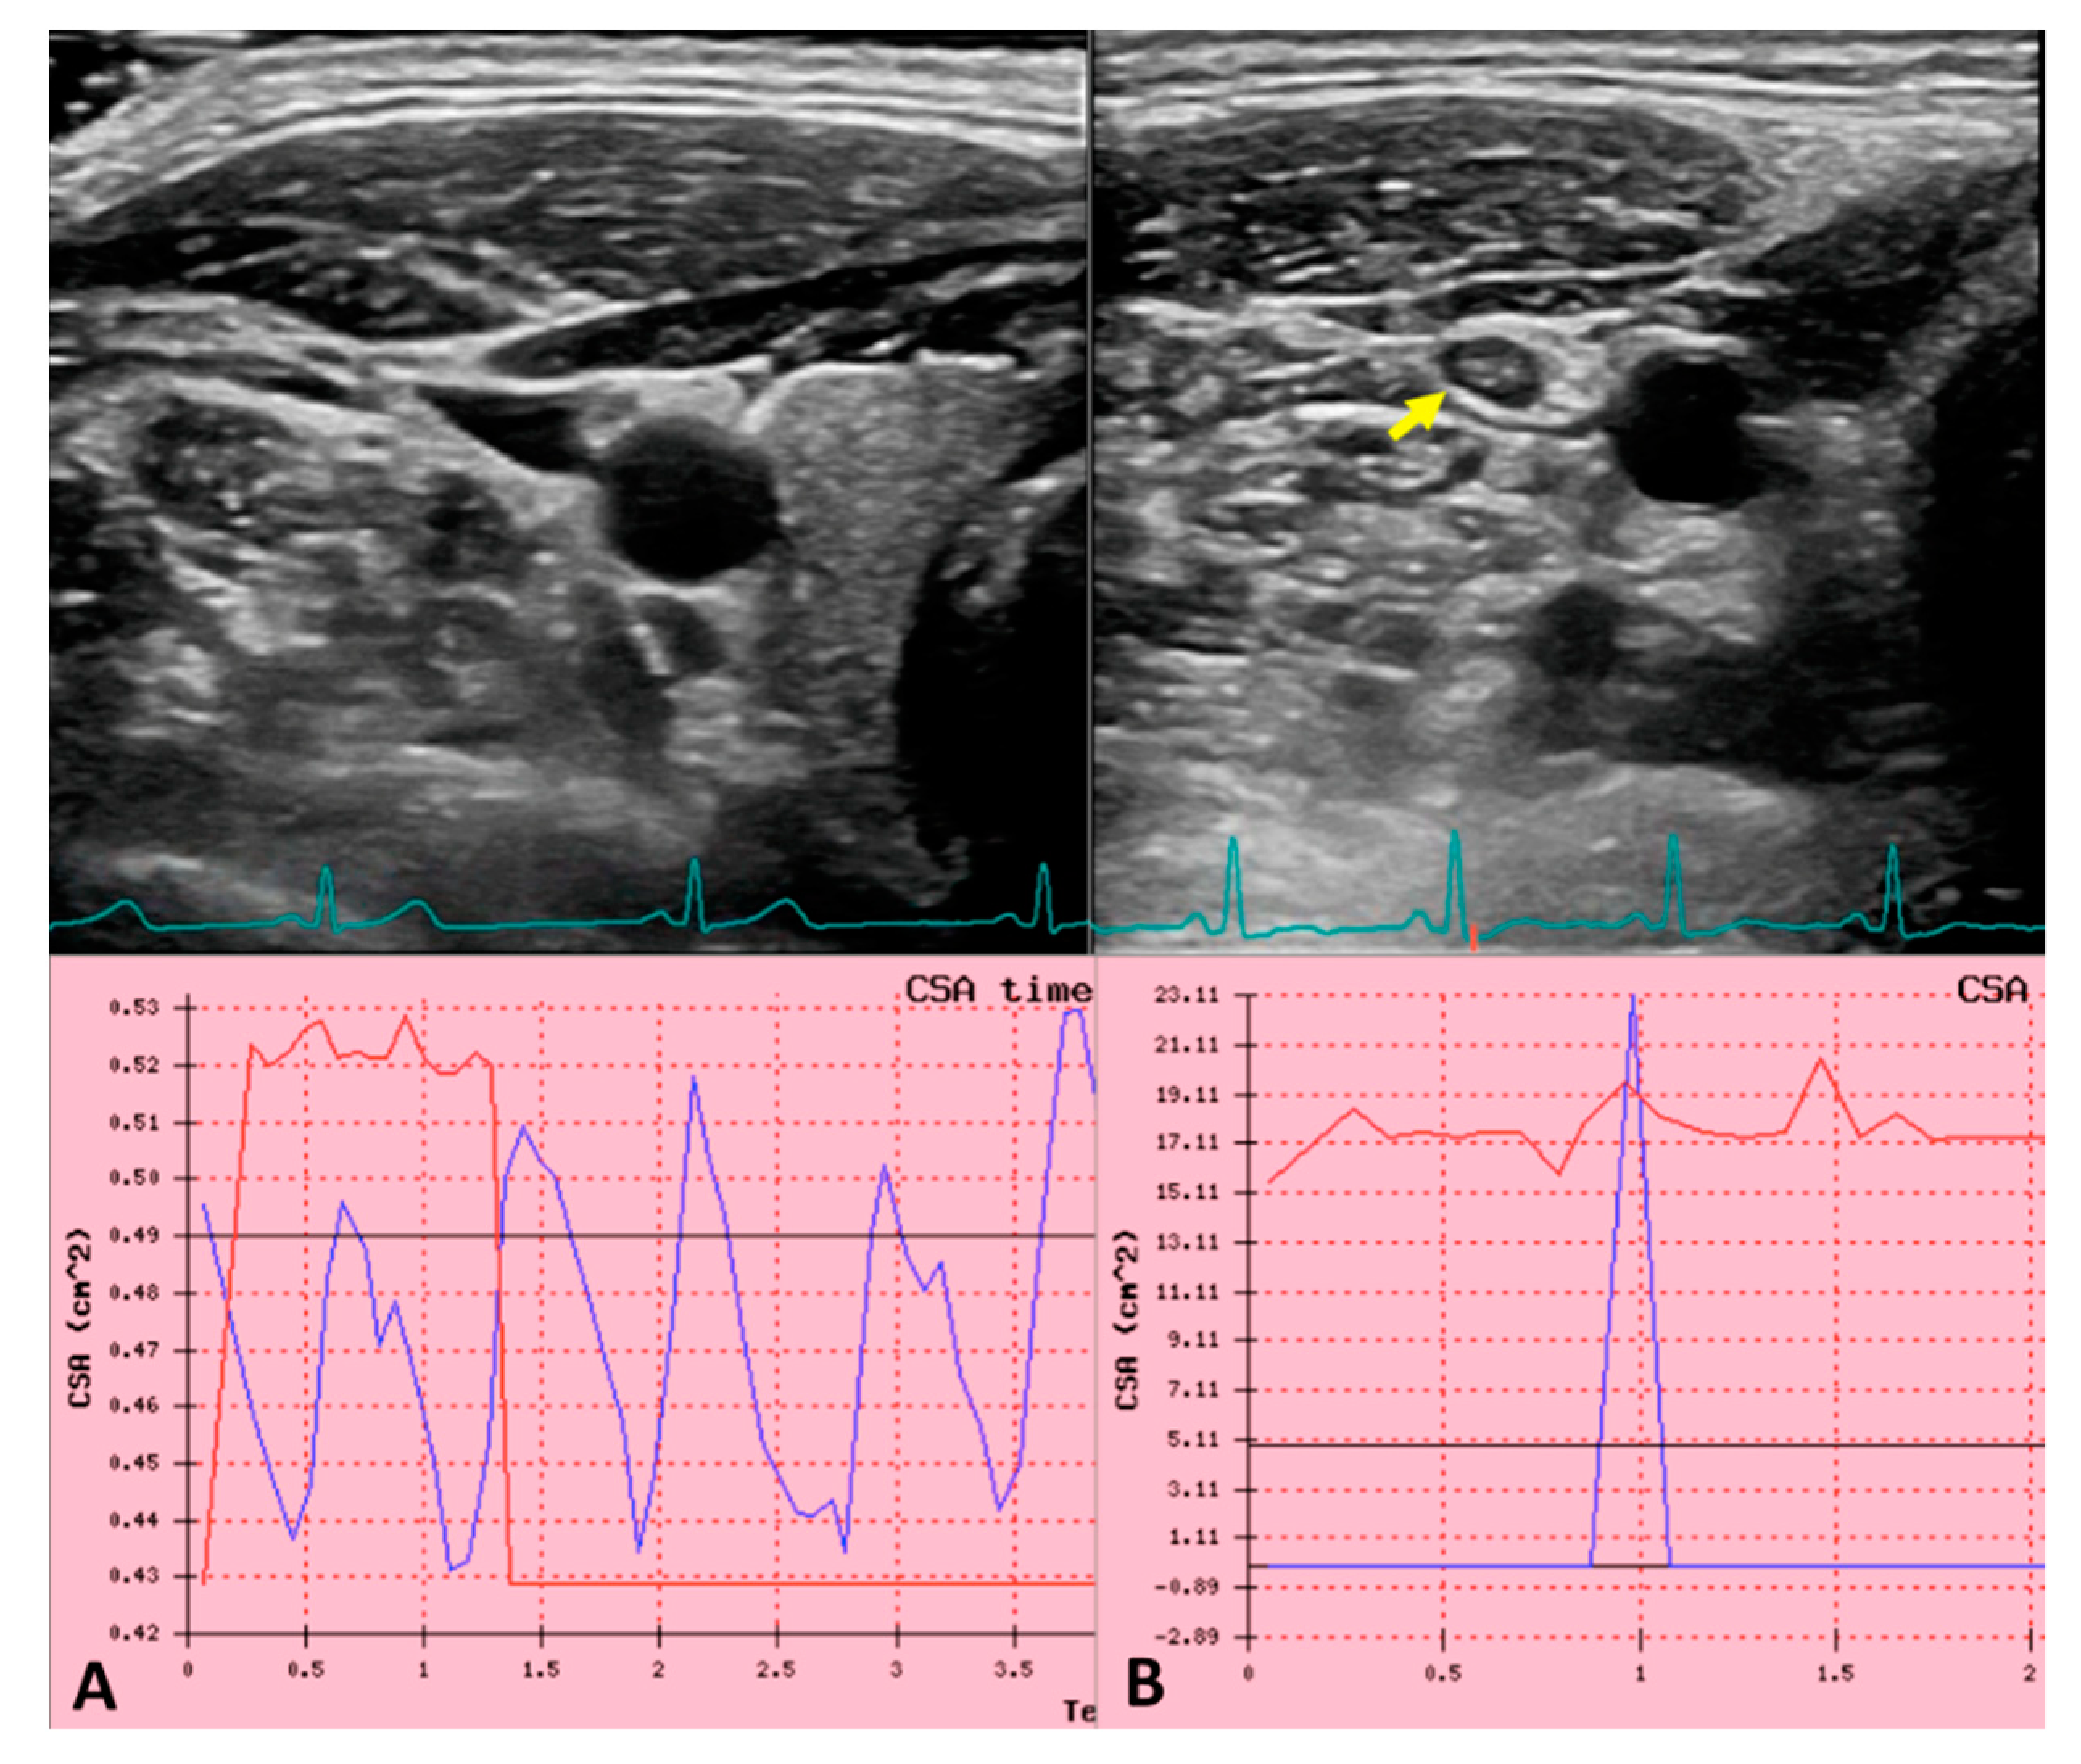

- Zamboni, P.; Sisini, F.; Menegatti, E.; Taibi, A.; Gadda, G.; Tavoni, V.; Malagoni, A.M.; Tessari, M.; Gianesini, S.; Gambaccini, M. Ultrasound Monitoring of Jugular Venous Pulse during Space Missions: Proof of Concept. Ultrasound Med. Biol. 2018, 44, 726–733. [Google Scholar] [CrossRef] [PubMed]

- Sisini, F.; Tessari, M.; Gadda, G.; Di Domenico, G.; Taibi, A.; Menegatti, E.; Gambaccini, M.; Zamboni, P. An Ultrasonographic Technique to Assess the Jugular Venous Pulse: A Proof of Concept. Ultrasound Med. Biol. 2015, 41, 1334–1341. [Google Scholar] [CrossRef]

- Zamboni, P.; Menegatti, E.; Conforti, P.; Shepherd, S.; Tessari, M.; Beggs, C. Assessment of cerebral venous return by a novel plethysmography method. J. Vasc. Surg. 2012, 56, 677–685.e1. [Google Scholar] [CrossRef] [PubMed] [Green Version]